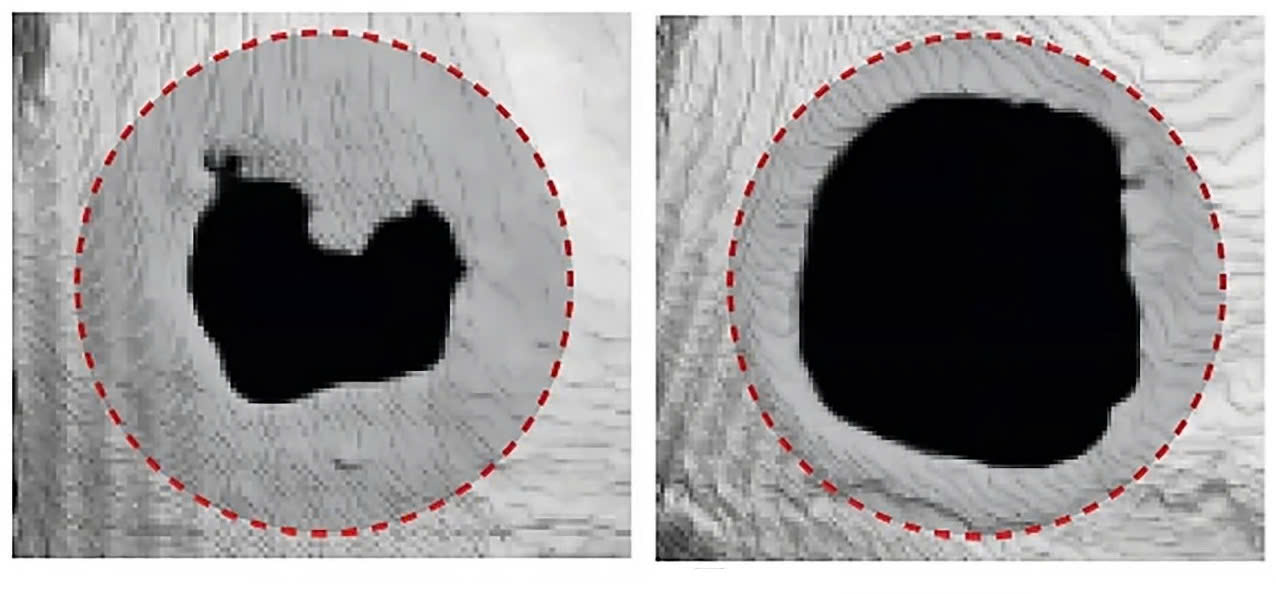

Khả năng tái tạo xương sọ sau khi tiêm tế bào Treg (trái) và không có (phải) Tregs (Nguồn: Newatlas).

Giáo sư Shizuo Akira - IFReC chia sẻ, so với những con chuột chỉ được tiêm hỗn hợp fibrin hydrogel không chứa Tregs thì những con được tiêm Tregs cho thấy lượng xương tăng lên và vùng bị thương ở sọ được phủ kín tốt hơn, số lượng mô cơ tăng lên và các sợi cơ lớn hơn, đồng thời vết thương trên da cũng được làm lành nhanh hơn. Khi nghiên cứu sâu về cơ chế của quá trình chữa lành do Tregs thúc đẩy, các nhà khoa học nhận thấy, Tregs có thể thích nghi với từng loại tổn thương cụ thể sau khi được đưa vào vùng bị tổn thương. Chúng biểu hiện mức độ cao các gen liên quan đến điều tiết hệ miễn dịch và chữa lành mô. Thử nghiệm thêm cho thấy, Tregs khiến các tế bào đơn nhân và đại thực bào trong mô bị thương chuyển sang trạng thái chống viêm, đặc biệt bằng cách tiết ra các phân tử tín hiệu như interleukin-10 (IL-10).